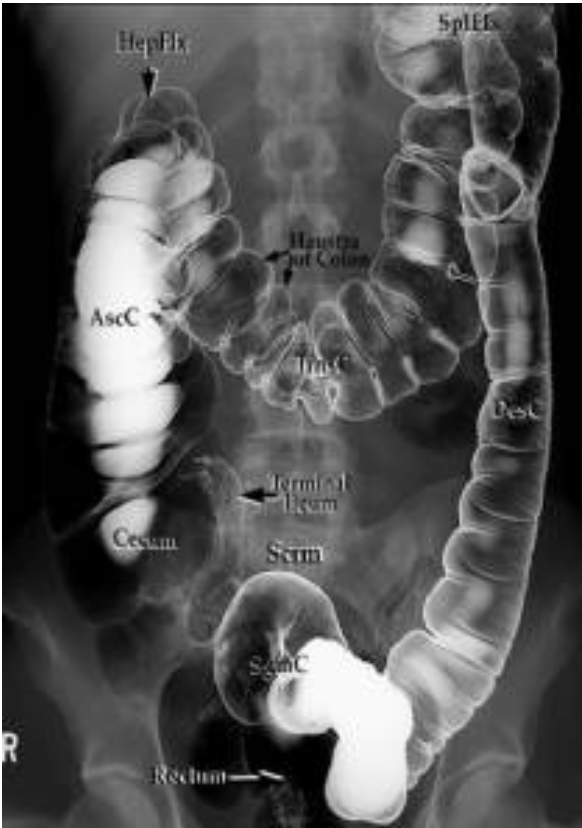

Haustra and Plicae

travel partial width of large bowel/colon

6cm for colon and 9cm for cecum is normal width

Abdominal Radiograph